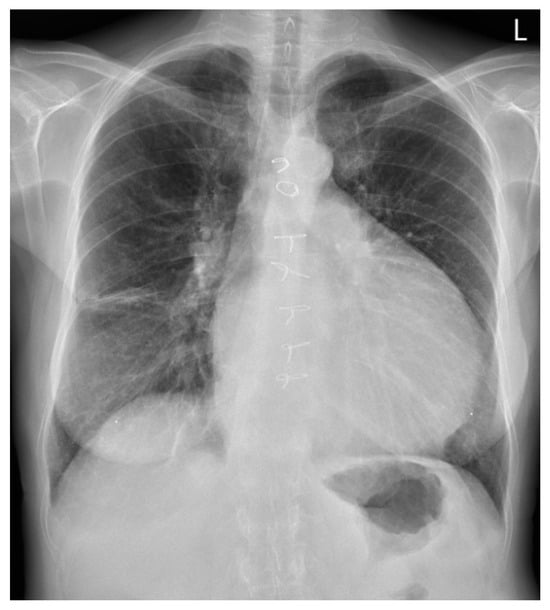

A 62-year-old female patient presented in October 2021 with an MI due to occlusion of the posterolateral branch of the circumflex artery. A conservative approach was chosen at the patient’s request. The patient remained entirely asymptomatic and clinically stabile in the following month. One month later, she was re-admitted to the hospital with dyspnea and a rapid and weak pulse. Auscultation revealed signs of pulmonary edema. At that time there was clinical concern for looming cardiogenic shock; however, hemodynamic and biochemical parameters remained within normal limits. Transthoracic echocardiography (TTE) revealed an impending LV free wall rupture with pericardial tamponade, necessitating emergency surgery. Intraoperatively, a posterolateral-located LV free wall rupture was observed. The infarcted and necrotic myocardial tissue surrounding the rupture site was debrided until viable margins were achieved. The distinction between viable and non-viable myocardium is often unclear, as the demarcation of necrotic tissue may not yet be apparent. Reconstruction was accomplished by securing a bovine pericardial patch over the defect using running sutures. The patient was weaned from cardiopulmonary bypass without incident. The postoperative course was uneventful. One year later, the patient was re-evaluated due to progressive symptoms of left-sided heart failure, most notably increasing dyspnea during minimal exertion and orthopnea. She reported a marked decline in exercise tolerance, becoming noticeably more fatigued and short of breath with activities that had previously posed no difficulty, such as walking short distances or performing light household tasks. She also reported recurrent episodes of syncope. The syncopal episodes were most consistent with orthostatic hypotension and were not associated with palpitations or other features of an arrhythmogenic origin. TTE showed a dilated left atrium and ventricle with decreased function and the presence of a LV pseudoaneurysm located at the posterolateral wall. Furthermore, moderate MR and mild tricuspid regurgitation (TR) were observed. During her follow-up in 2023, she missed her biannual outpatient appointments. By the year’s end, she began experiencing increasing heart failure symptoms (New York Heart Association, class II). Routine blood tests including troponin, leukocyte count, and C-reactive protein were within normal limits. A subsequent TTE showed worsening of her MR and TR, alongside with pulmonary hypertension. More importantly, the TTE also revealed the pseudoaneurysm had increased in size, displaying a broad neck and exerting mass effect on adjacent structures. A chest X-ray, as shown in Figure 1, revealed a markedly enlarged cardiac silhouette, with a cardiothoracic ratio exceeding 0.5, and a conspicuously dilated LV contour. Additionally, Kerley B lines were observed in the right lateral lung field, accompanied by linear pleuropulmonary opacities, indicative of interstitial congestion. Consequently, she was referred from her hospital to our multidisciplinary Heart Team for high-risk patients, where she was accepted for re-operation: LV pseudoaneurysmectomy, mitral valve repair, and tricuspid valve repair.

Figure 1. Posteroanterior chest X-ray showing marked cardiomegaly, predominantly due to the pseudoaneurysm.